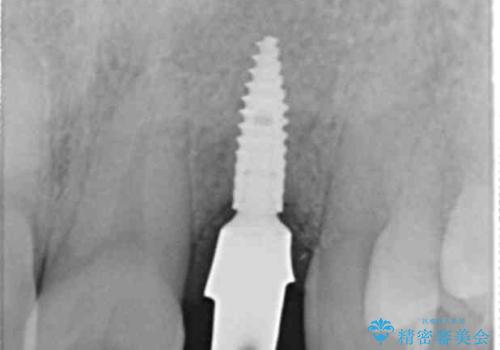

- 55万円(ストローマンインプラント・ジルコニアカスタムアバットメント・骨造成・仮歯・ジルコニアクラウン)費用は治療当時の料金となります

前歯部にインプラントを埋入し、きれいに仕上げるためには骨の造成技術や歯肉の厚みを増すような処置を行い、インプラント周囲の環境を整備することが肝要です。